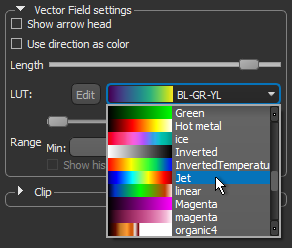

- Choose another look-up table (LUT) in the LUT drop-down menu.

NOTE The Jet LUT is often a good color scheme choice. In this LUT, vectors corresponding to the highest surface anisotropy are colored red, while those corresponding to the lowest, or are isotropic, are colored blue.